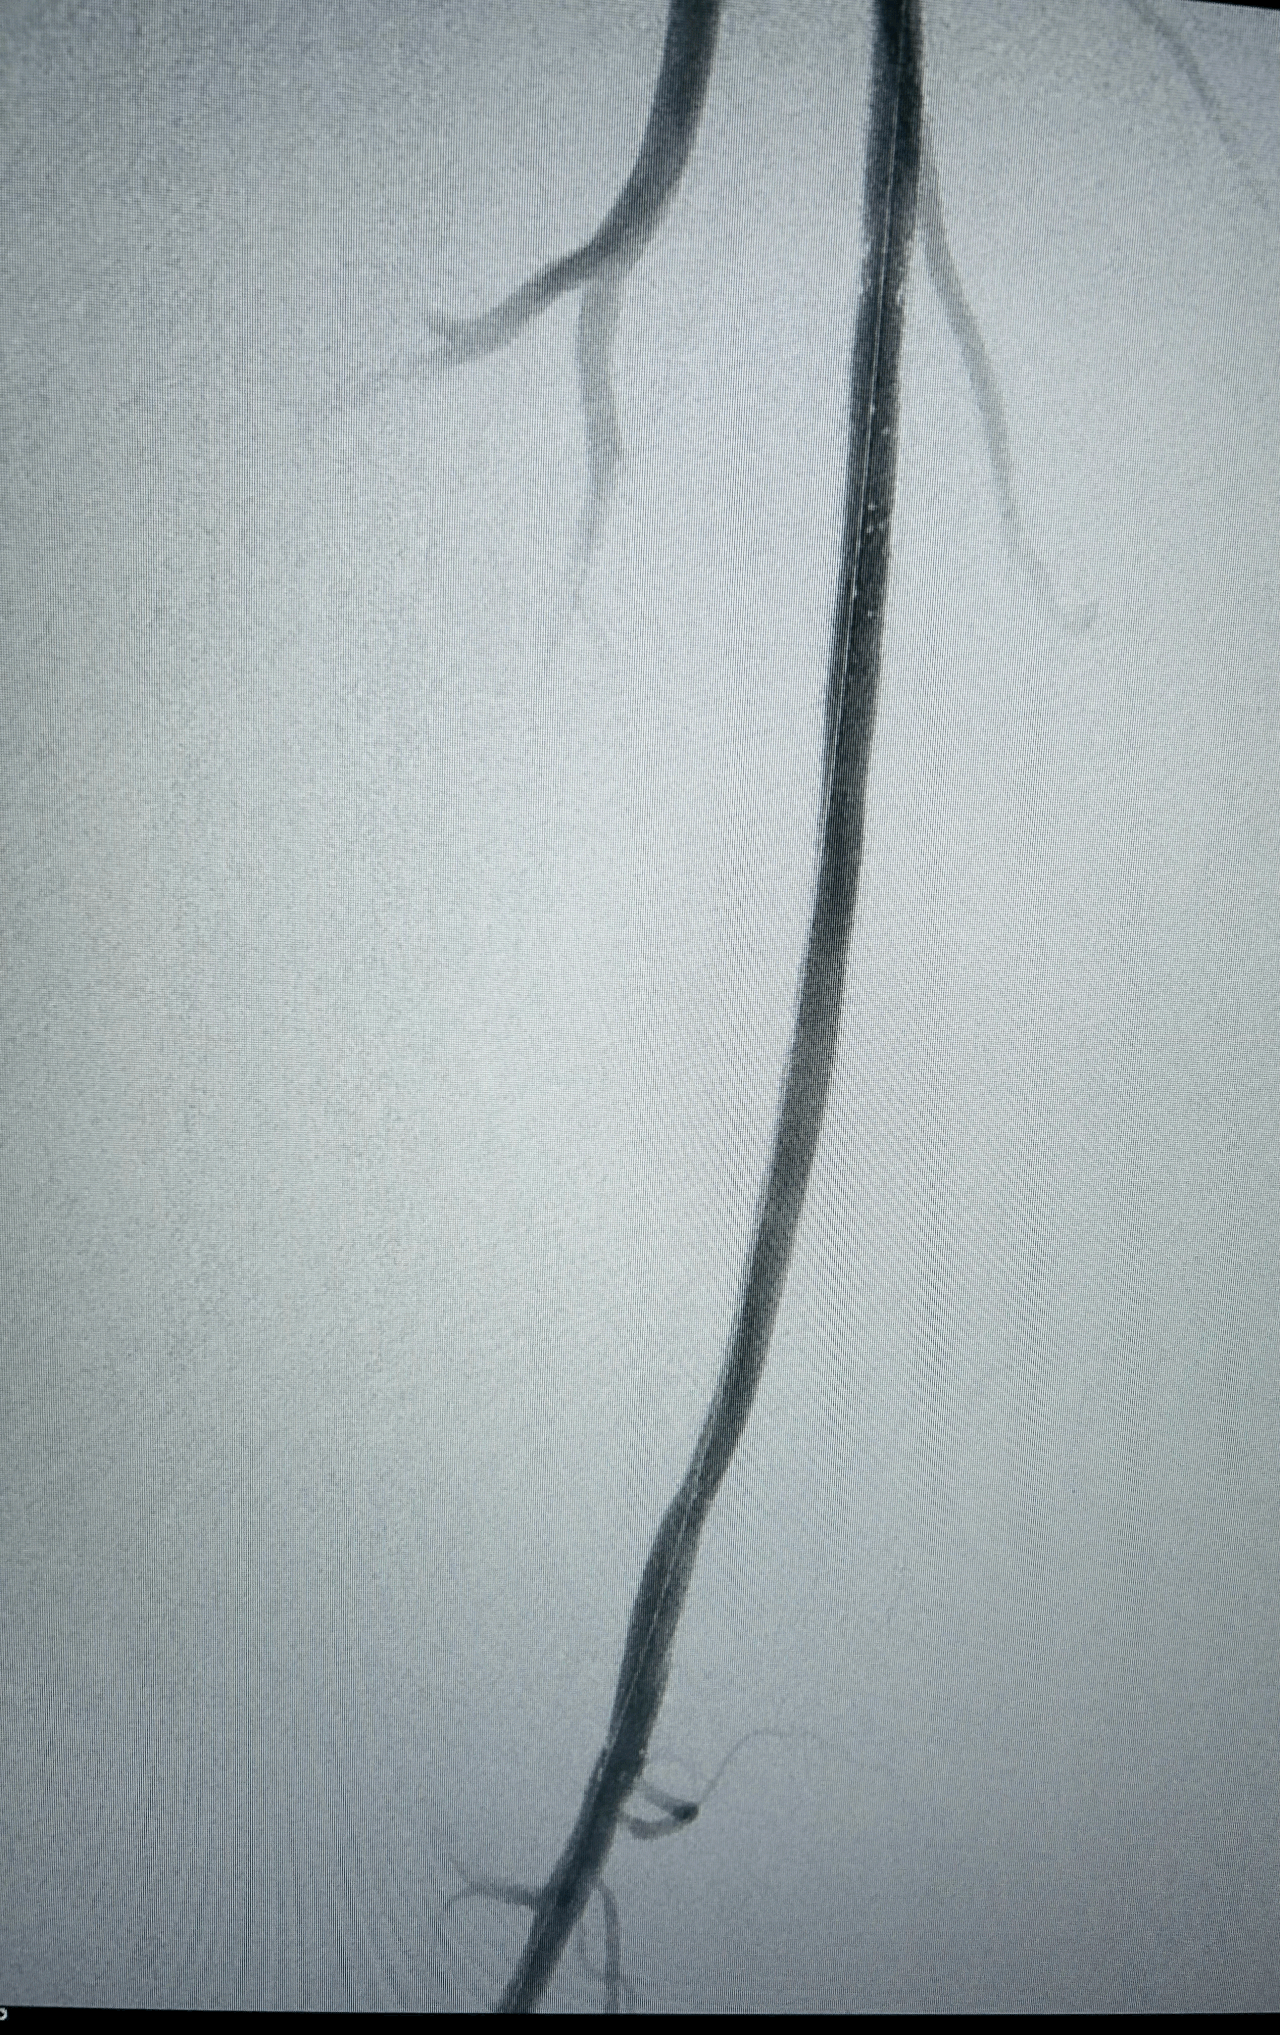

Excellent résultat anatomique immédiat au contrôle artériographique per-opératoire.

Respect de la perméabilité de l'ostium de l'artère fémorale profonde et de ses collatérales au niveau de la jonction fémoro-poplitée.

Aucune embolisation distale per-opératoire constatée au niveau des artères de jambe et du pied.

Très bonne revascularisation clinique du pied et excellent pouls tibial postérieur droit.